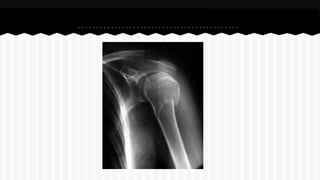

RESPONDA O NOME DO OSSO EM QUE

SE ENCONTRA A (S) FRATURA (A).